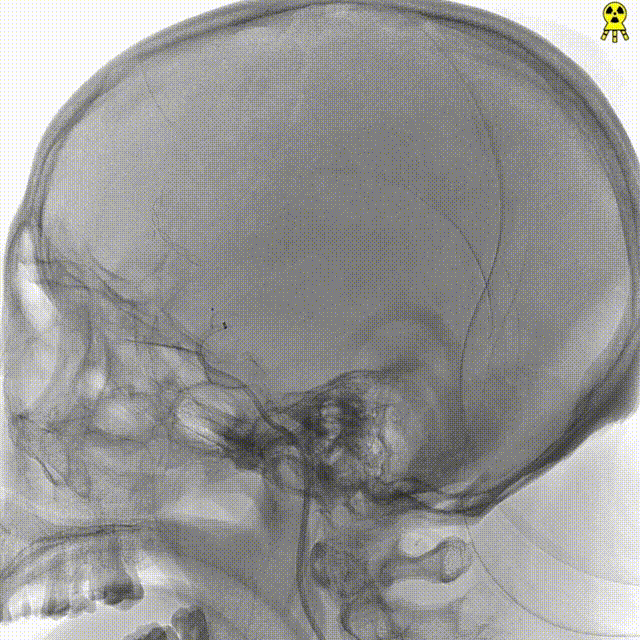

右侧颈内正位造影

右侧颈内侧位造影

载瘤动脉远端血管直径:2.1mm

载瘤动脉近端血管直径:1.8mm

动脉瘤尺寸:瘤颈4.69mm,大小3.25mm*4.21mm*4.24mm;指向右上

近端狭窄:最窄处:0.53mm,远心端2.1mm,近心端2.2mm,长度11.23mm